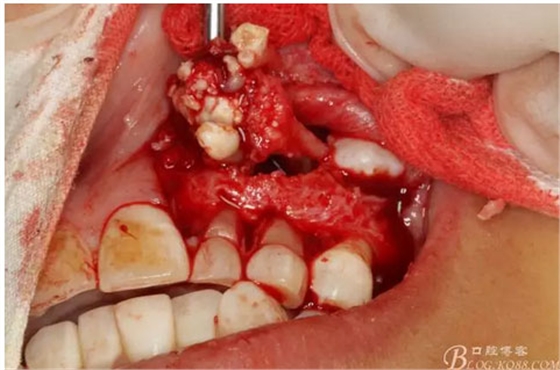

圖12.用小骨鑿去除覆蓋在牙瘤表面的骨質(zhì)。發(fā)現(xiàn)牙瘤的包膜。

圖13.暴露出部分牙瘤

圖14.沿一側(cè)骨壁逐步剝離牙瘤組織。

圖17.呼之欲出的巨大牙瘤組織。